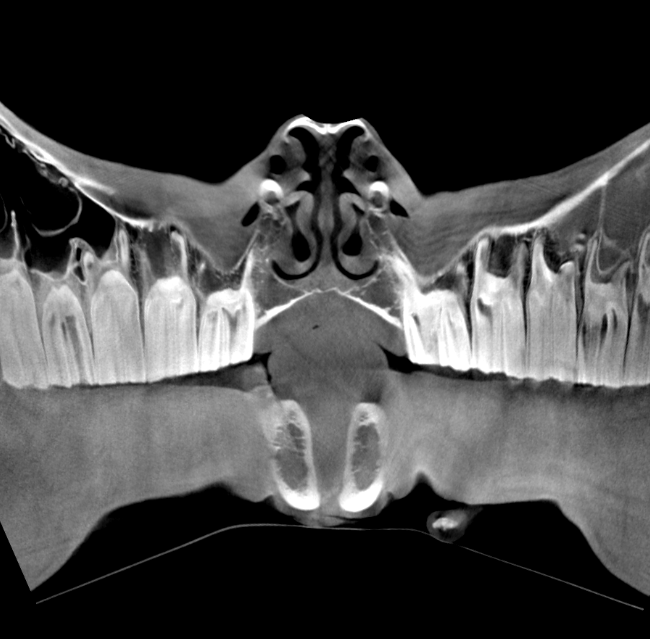

Our High Definition Volumetric Imaging (HDVI) technology represents the most advanced stage of Flat Panel CT technology. It offers exceptional diagnostic imaging for both hard and soft tissues, in diagnostic settings and intraoperative theaters. It is the gold standard for orthopedic applications.

Pegaso enhances safety and usability by enabling the scanning of a standing horse’s head, neck, and limbs.

Scan of the standing horse

Pegaso scans head, neck and limbs of the standing horse